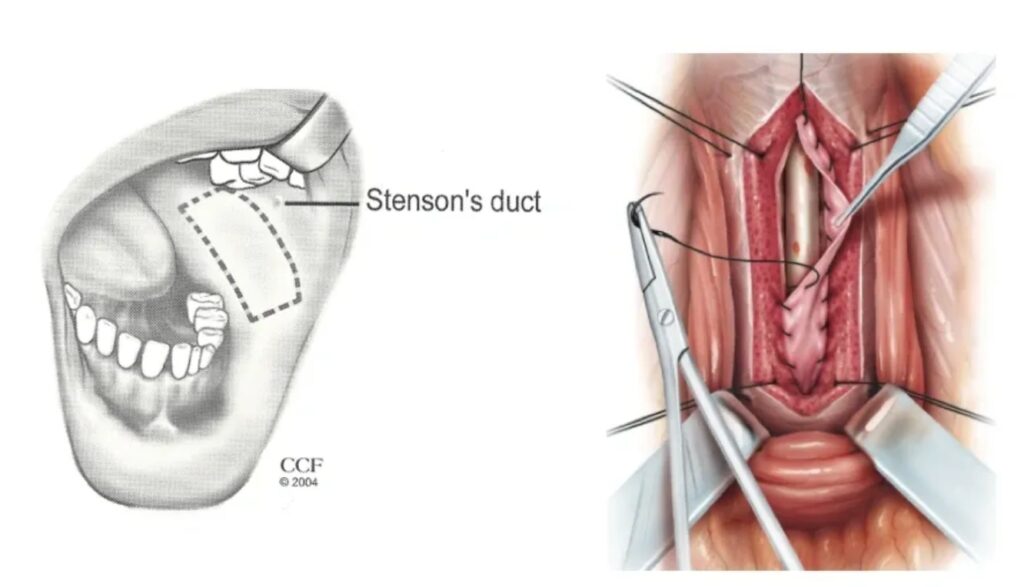

URETROPLASTIA PARA ESTENOSE DE URETRA

A Estenose de uretra é uma doença que compromete significativamente a qualidade de vida da pessoa.

Quando não tratada o paciente pode requerer o uso de sonda vesical ou cistostomia indefinidamente

As opções de tratamento depende da localização e a gravidade da estenose.

A Uretrotomia interna e a Uretroplastia com enxerto de mucosa oral são as algumas das técnicas reconstrutivas para o tratamento da estenose uretral.